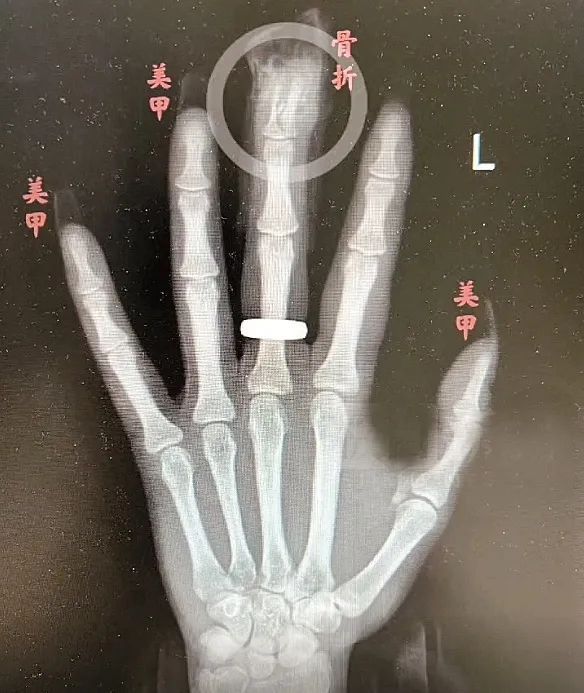

“两根手指末端指骨粉碎性骨折,甲床破裂。”在武汉市第四医院古田院区,医生用一根克氏针复位固定了王玥骨折的手指,并用极细的手术缝合线缝合甲床。幸运的是,王玥指尖末端血供不错,术后恢复较好。但由于骨折严重,术后还需要康复锻炼才能争取恢复指尖的屈曲功能,而且甲床受损,半年后重新长出来的指甲可能会不复以前的平整美观。

王玥手指骨折术后康复中。

王女士甲片长度是正常指甲长度的2倍,又有一定向下的弧度,在摔倒的瞬间,冲击力较大,手指触地时指甲比手掌更早接触地面,再加上甲片被胶水牢牢固定,“就像个杠杆,直接掀翻指甲,还导致指骨骨折。”冯伟医生表示,如果没有美甲,伤害不会这么严重。

春节前,王玥美美地做了一款美甲,还特意选择贴了延长甲片让手指显得更为修长。不料,骑电动车时意外摔了一跤,“手指触地瞬间一阵剧痛,我一看好几个甲片翻起来了,有两个指头血直流。”